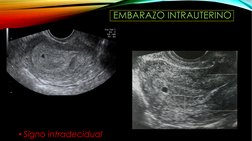

EMBARAZO INTRAUTERINO

• Signo intradecidual